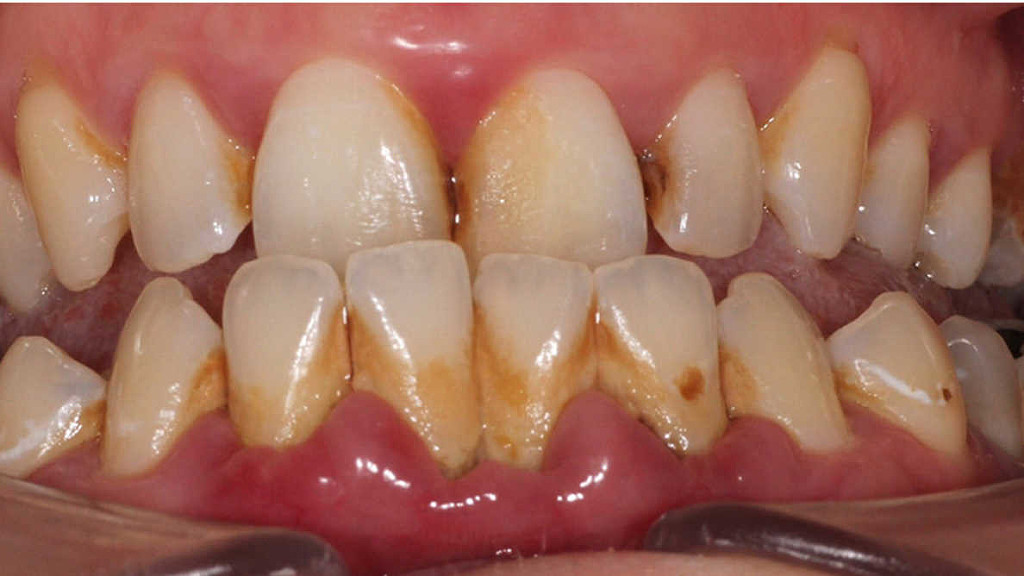

One common example of a biofilm dental plaque, a slimy buildup of bacteria that forms on the surfaces of teeth. Pond scum is another example. Biofilms have been found growing on minerals and metals. They have been found underwater, underground and above the ground. They can grow on plant tissues and animal tissues, and on implanted medical devices such as catheters and pacemakers.

Oral biofilm is medically important because it has broad implications for maintaining not only oral health but also systemic health. It is estimated that biofilms account for over 80% of microbial infections in the body. Research has undoubtedly shown that biofilm-dependent infections, including oral diseases such as caries, and periodontal and endodontic disease, thus pose major public health and cost concerns globally.

Periodontal disease, in particular, is considered one of the most prevalent diseases worldwide, affecting up to 50% of the world’s adult population, according to FDI World Dental Federation. Previous research has established connections between periodontal disease and preterm births, low birthweight, diabetes, and risk factors associated with cardiovascular disease and stroke. Globally, periodontitis is responsible for an estimated US$54 billion per year in lost productivity and a major portion of the US$442 billion spent annually on oral disease, according to the European Federation of Periodontology.